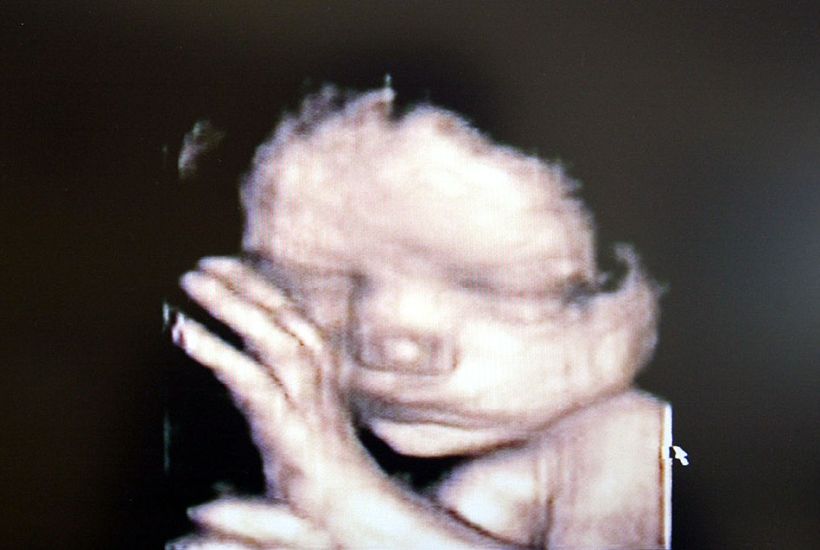

The Faruqi bill removes all prohibitions against unlawful abortions without proposing any regulation to fill the gaps or address the issues this creates. It legalises abortions at any stage of pregnancy, for any reason. To be clear, that means it would be entirely legal to perform an abortion on a nine-month-old, fully viable unborn baby an hour before birth.